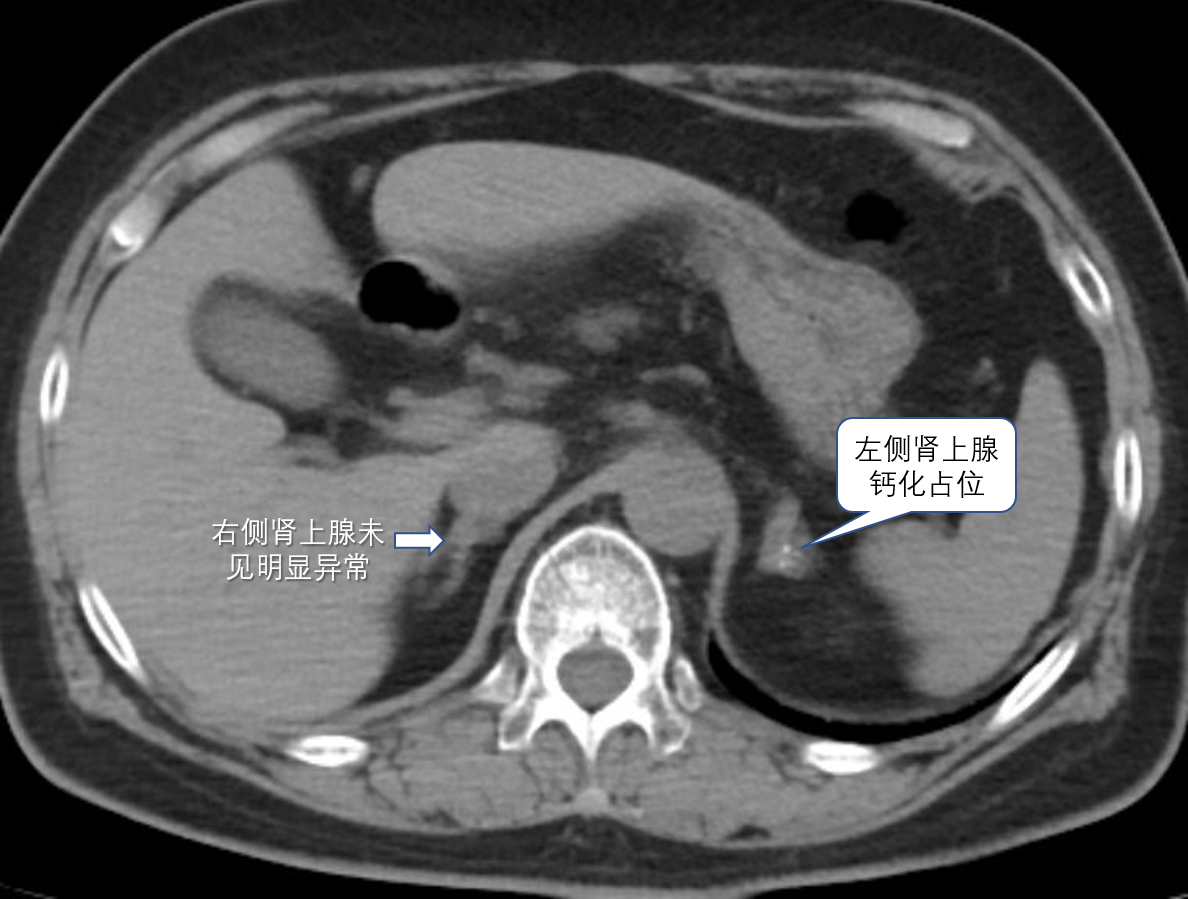

60岁的林阿姨(化名),10前发现血压升高,最高血压到180/100mmHg,反复有头昏不适,通过饮食控制、运动、吃药等多种方式,降压效果时好时坏。直到近期感觉身体乏力、心慌,到家附近医院检查发现血钾偏低,血压波动大。当地医生为林阿姨做了一系列高血压的病因筛查。不查不知道,一查吓一跳!医生告诉林阿姨:她得了原发性醛固酮增多症,CT检查还发现她的左侧肾上腺长了一个约28×27mm的瘤,考虑醛固酮瘤导致的高血压,建议行外科行手术切除。

在充分沟通、完善术前评估后,心内科介入团队为林阿姨实施了高难度的双侧肾上腺静脉采血术,手术顺利,成功采血!随后检验科给出的化验结果却出人意料:右侧肾上腺明显异常分泌,而左侧肾上腺(长腺瘤的一侧)无明显分泌。经过与检验科反复核对,结果仍如此,也就是说,从AVS的结果看,她的醛固酮增多并不是CT上看到的那个左侧肾上腺腺瘤引起的。手术直接切除这个瘤,不仅产生手术创伤,而且对血压血钾控制并没有好处。